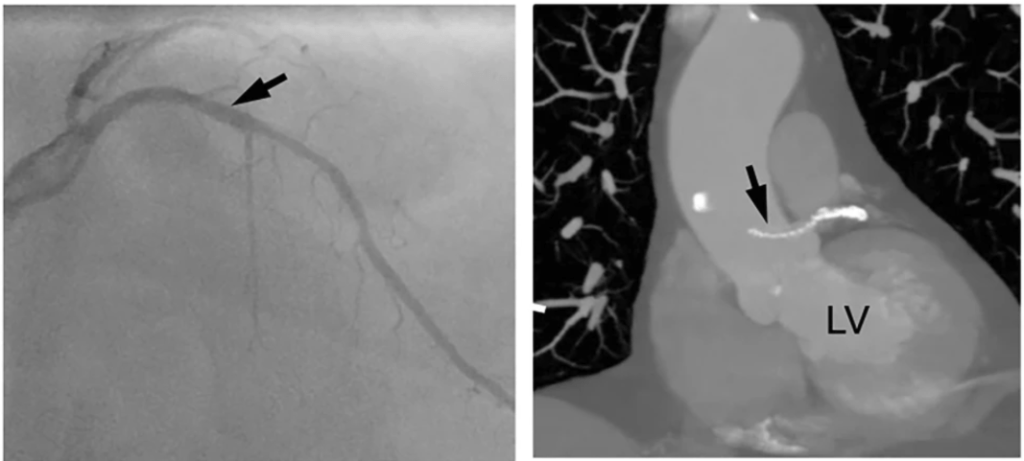

A LAD stent migrates retrogradely into the aortic root crossing the left main ostium. Image source and courtesy Hilary Bews and others, Coronary stent on the move, European Heart Journal – Case Reports, Volume 5, Issue 12, December 2021, ytab511, https://doi.org/10.1093/ehjcr/ytab511